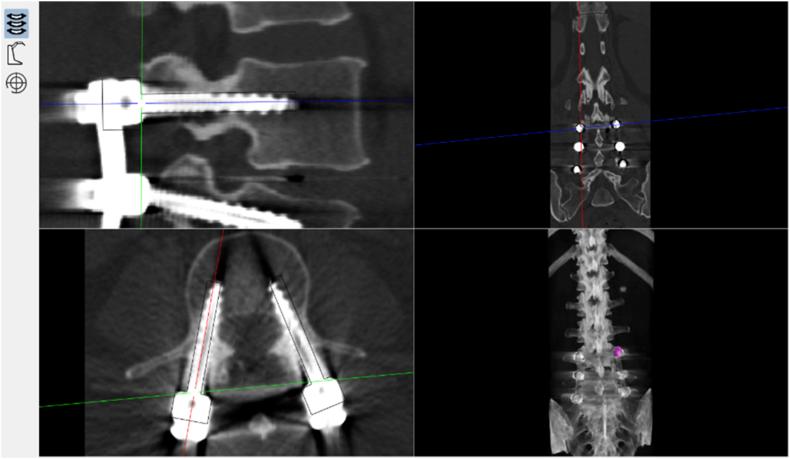

A total of 82 pedicle screws were placed in the 17 participants. In the RA group, 90.6% of screws placed were Grade A, and 9.4% were Grade B. In the FH group, 78.0% of screws were Grade A, 20.0% were Grade B, and 2.0% were Grade C. No statistical difference was found in the operation time, radiation time per case, and length of stay between both groups. The radiation time per screw is significantly lower in the RA group. No screw-related complications or revision occurred in the present study.

The outcome of screw accuracy of this robotic system was comparable with that of experienced surgeons, and no screw-related complication was found in the RA group during hospitalisation. In addition, radiation time per screw in the robotic group was significantly lower than that in the conventional group, which shows the potential to reduce radiation exposure of pedicle screw fixation assisted by this robotic system.

Our study shows that pedicle screw fixation assisted by "Orthbot" system is accurate and safe. It is concluded that this novel robotic system offers a new option for internal implantation in spine surgery.

17名参与者共植入82枚椎弓根螺钉。在RA组中,90.6%的植入螺钉为A级,9.4%为B级。在FH组中,78.0%的螺钉为A级,20.0%为B级,2.0%为C级。两组之间的手术时间、每例辐射时间和住院时间均无统计学差异。RA组每枚螺钉的辐射时间显著更低。本研究中未发生螺钉相关并发症或翻修情况。

该机器人系统的螺钉植入准确性结果与经验丰富的外科医生相当,且RA组在住院期间未发现螺钉相关并发症。此外,机器人组每枚螺钉的辐射时间明显低于传统组,这表明该机器人系统辅助下的椎弓根螺钉固定具有减少辐射暴露的潜力。

我们的研究表明,“Orthbot”系统辅助下的椎弓根螺钉固定准确且安全。得出结论,这种新型机器人系统为脊柱手术的内固定植入提供了一种新选择。